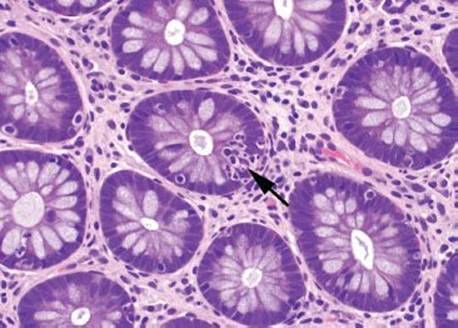

Figure 4.16 Focal active colitis pattern. Except for an isolated collection of neutrophils invading the crypt epithelium (arrow), this colonic biopsy appears essentially normal; the background crypts are evenly spaced and orderly.

Focal active colitis (FAC) is a histologic pattern characterized by single foci of neutrophilic crypt injury without features of chronic injury (chronicity) (Figs. 4.16–4.23). The pattern encompasses a spectrum of histologic changes, ranging from a single crypt abscess (neutrophils in the crypt lumen) and single focus of cryptitis (neutrophils in the crypt epithelium) to multiple discrete foci of cryptitis, or even crypt abscesses within a series of colorectal biopsies.3Segmental distribution and features of architectural distortion and chronicity are absent, by definition. Similar to most patterns, the FAC pattern does not represent a discrete disease entity, but instead represents multiple clinical prodromes that have similar histologic features. These include acute self-limited colitis, inflammatory bowel disease, ischemic colitis, irritable bowel syndrome, bowel preparation artifact, antibiotic-associated colitis (i.e., Clostridium difficile colitis), and medication injury (i.e., nonsteroidal anti-inflammatory drugs, NSAIDs). Among these patients, clinically significant diarrhea is the most common indication for colonoscopy; however, FAC is also an incidental finding in asymptomatic patients undergoing routine cancer surveillance colonoscopy. As a result, determining the significance of FAC requires correlation with clinical and microbiologic information.